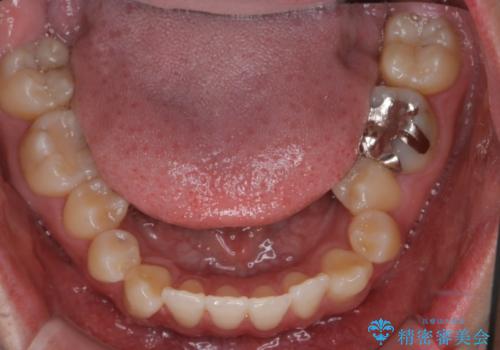

- 右上2番が欠損しており、歯並びをバランスよくしたいということで来院されました。

ワイヤー装置とマウスピースで悩まれていましたが、マウスピースで治療可能と判断致しましたのでマウスピースにて治療しました。

IPR、歯列弓拡大、ゴム掛けを行い歯並びを整える治療計画を立てました。

右上2番が欠損しているため、見た目と噛み合わせの両方のバランスを整えるために経過を追いながら必要な部位にゴム掛けをしました。

また矯正後、患者様の希望で

メタルインレーをセラミックインレーにやりかえさせていただき、さらに綺麗に仕上がりました。